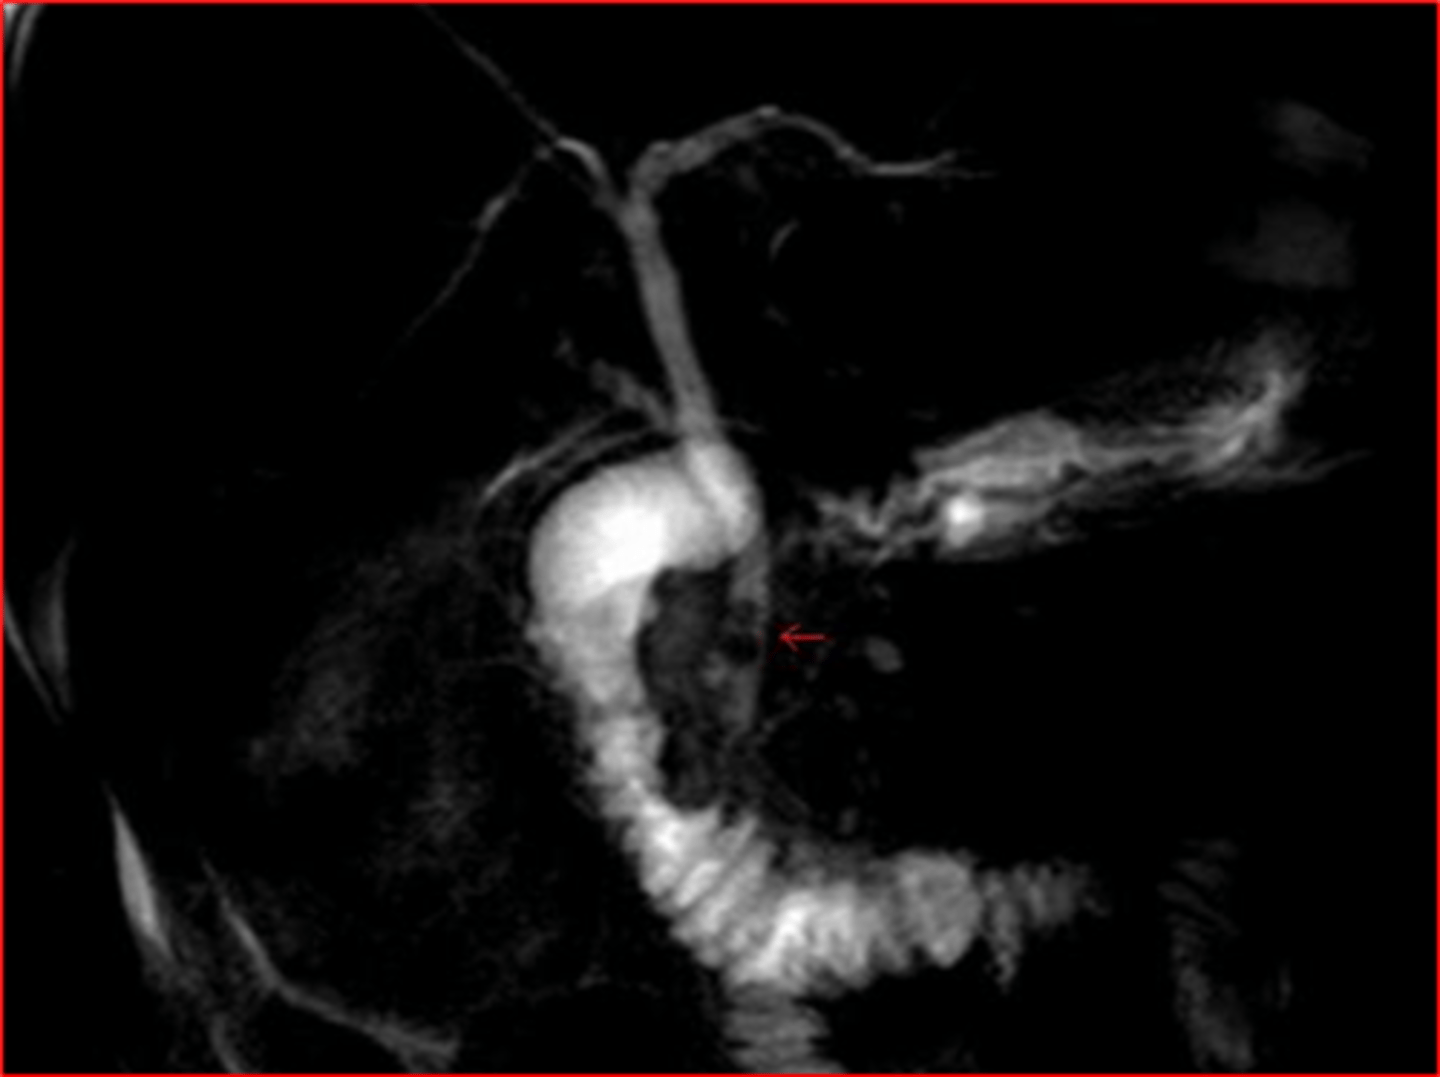

noninvasive method to image biliary tree without requiring the injection of contrast or dye

MRCP

T2 fluid filled structures appear _______ on magnetic resonance cholangiopancreatography (MRCP)

bright white